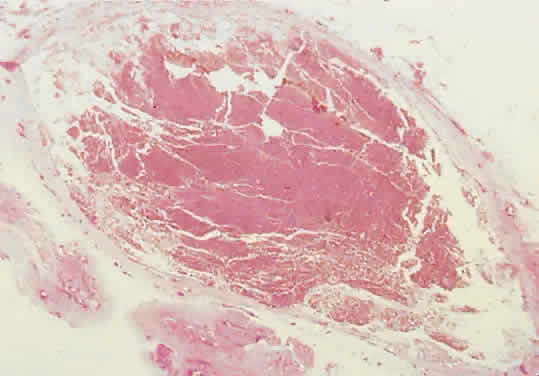

are each defined by thin septa lined by endothelial cells (Fig. 11). The lumens contain proteinaceous material that probably represents local

transudation. This fluid has the appearance, if not the physiologic

function, of lymph. The designation of these lesions as lymphatic malformations

of the intercommunication of vascular channels (Fig. 12). The sparse stroma allows dramatic expansion of blood cysts.  Fig. 11. The labyrinthine structure of a lymphangioma appears as multiple microcysts

in histologic sections. The lumens contain pale staining lymphlike

fluid. The channels extend into surrounding normal tissue without circumscription

or encapsulation (hematoxylin-eosin; × 40). Fig. 11. The labyrinthine structure of a lymphangioma appears as multiple microcysts

in histologic sections. The lumens contain pale staining lymphlike

fluid. The channels extend into surrounding normal tissue without circumscription

or encapsulation (hematoxylin-eosin; × 40).

Fig. 12. Bleeding into a lumen produces a hemorrhagic macrocyst. The sparse stroma

and absence of a tumor capsule permit dramatic expansion, and proptosis

may appear abruptly in a previously unrecognized case (hematoxylin-eosin; × 15). Fig. 12. Bleeding into a lumen produces a hemorrhagic macrocyst. The sparse stroma

and absence of a tumor capsule permit dramatic expansion, and proptosis

may appear abruptly in a previously unrecognized case (hematoxylin-eosin; × 15).